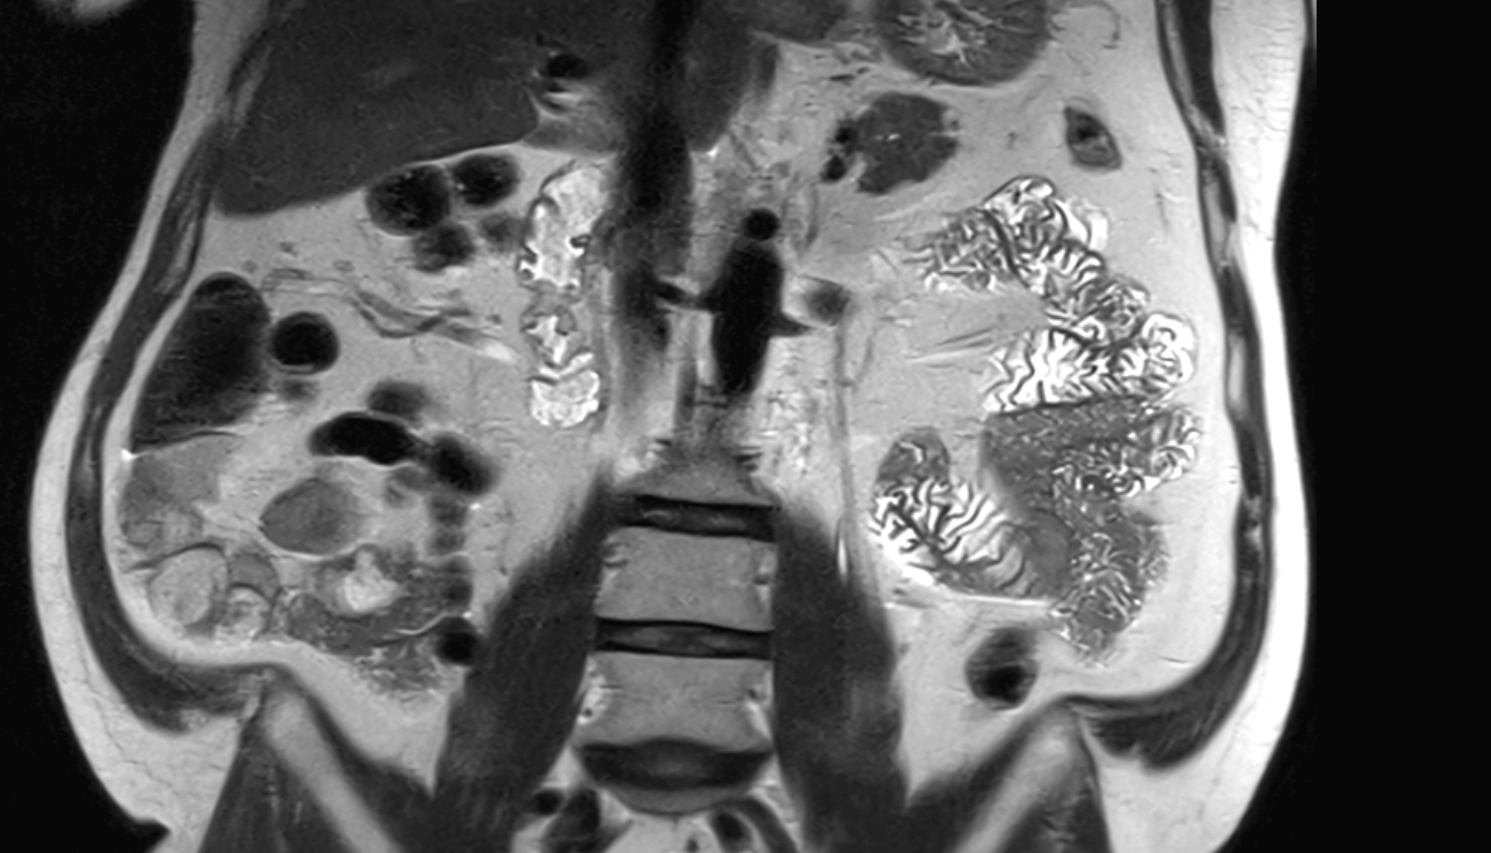

- kidneys

- Right kidney

- Left kidney

- Kidney cortex (Renal cortex)

- Renal capsule

- Renal medulla

- Renal pyramids

- Adrenal gland

- Ureters

- Left ureter

- Right ureter

- Renal artery

- Renal vein

- Left renal vein

- Right renal vein